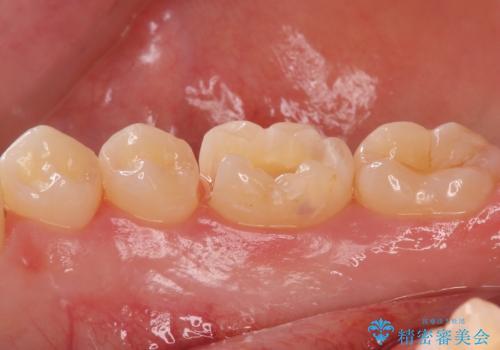

矯正後の虫歯治療 セラミックインレーでの治療

- 矯正後の虫歯治療です。

咬む面と歯と歯の間の虫歯に対してセラミックインレーでの修復処置をしていきます。

- 右下6 セラミックインレー 77,000円費用は治療当時の料金となります

下の奥歯は外から見える場所です。審美的なセラミックでの治療をおすすめします。